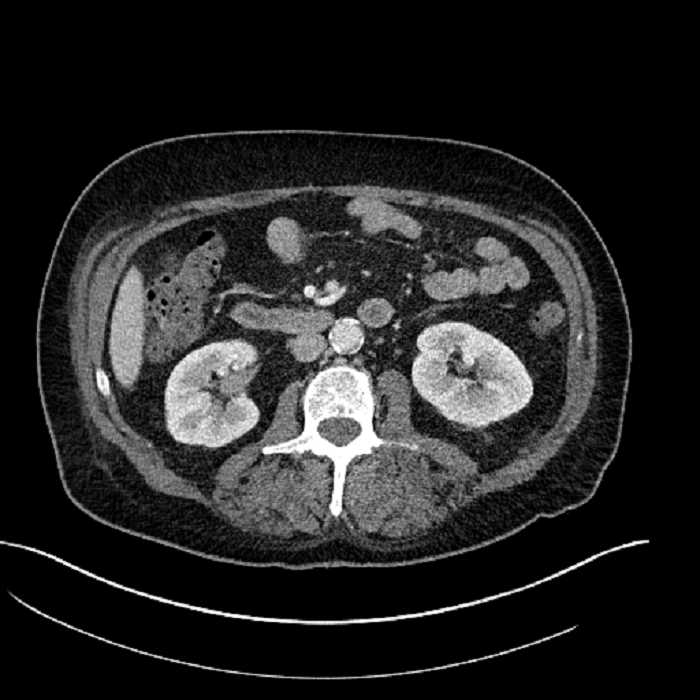

Age: 63

Sex: Male

Indication: Abdominal pain

• Large fluid density structure in hepatic segments 7 and 8 measuring 10 x 7 x 7 cm with internal septation and circumferential ill-defined low density compatible with edema

• Peripherally enhancing subcapsular collections along the anterior margin of the left hepatic lobe measuring 3 x 1 cm and 2 x 1 cm

• Clearly marginated fluid density structure in segment 7 and several other scattered tiny hypodensities, which likely represent cysts

• Hepatic abscess

Acute sigmoid diverticulitis complicated by a small contained perforation and a large abscess in the right hepatic lobe. Additional small subcapsular abscesses along the anterior margin of the left hepatic lobe.

• The classic CT imaging appearance is a double target sign with internal low density surrounded by an internal enhancing rim (capsule) and a low density external rim (edema)

Hepatic abscess showing the double target sign with low density internally surrounded by a thin inner enhancing rim (red arrow) and ill-defined outer low density rim (yellow arrow). Blue arrow indicates an internal septation. Red arrows: additional smaller subcapsular abscesses. Red arrow: focal contained perforation associated with diverticulitis.